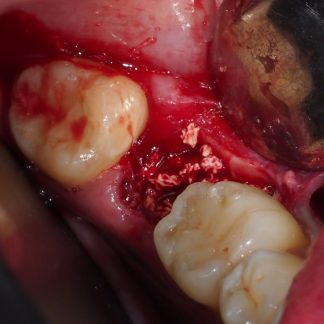

- Preparación de lecho oseo con agujeros de decorticalización

- Colocación de membrana Jason

- Colocación de gránulos de hueso